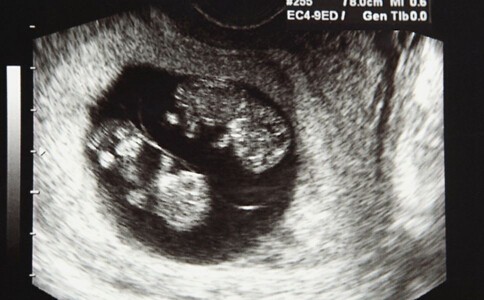

怀孕第13周双胞胎B超图

眼睑:这时宝宝们的眼睑不再那么透明了,双眼也挪得更近了。

脐带:宝宝们的肠子发育速度很快,突进脐带了,不过它现在开始缩回腹腔。

耳朵:宝宝的耳朵更加接近头部两侧的最终位置了。

子宫:你的子宫的顶部(子宫底)开始抬升到骨盆上方;你可能注意到了自己的腰正在变粗。